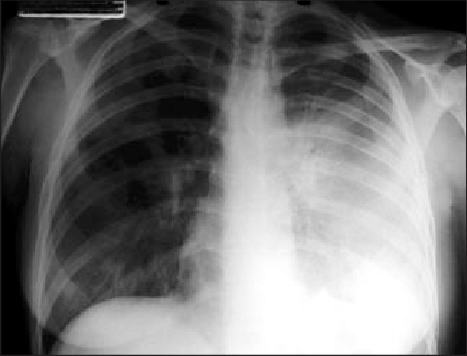

- Neumonía que rápido evoluciona con dificultad para respirar, dolor en el pecho, tos y, a veces, mucosa con sangre o agua.

- La neumonía puede causar insuficiencia respiratoria y shock.

La peste neumónica es la única forma de peste que se puede transmitir de persona a persona y es la forma más grave de la enfermedad.